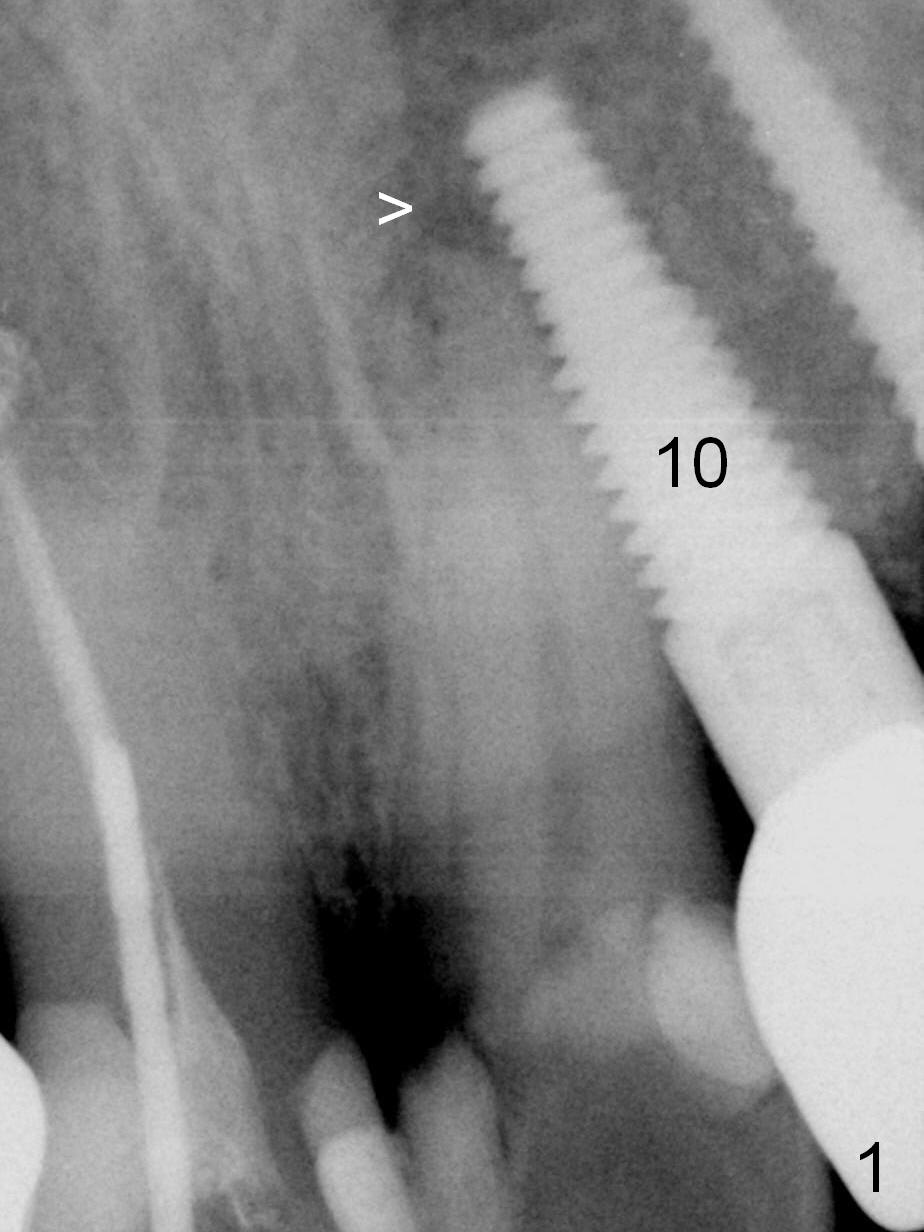

How to avoid apparent iatrogenic damage to the neighboring root? Preop PA shows approximation of these roots (Fig.2). Unfortunately the initial osteotomy is too mesial (Fig.3), which is unnoticed. When a 4.5x17 mm implant is placed, there is distal gap (Fig.4 <), while the mesial one is closed.

When the two neighboring roots are close to each other, start the osteotomy distally (Fig.5,6) particularly for the site at the distal end.